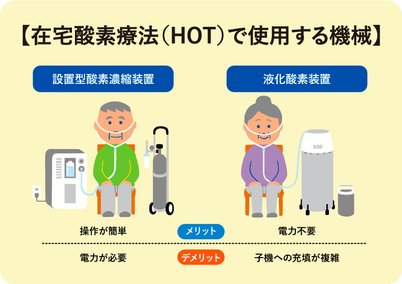

在宅酸素療法 HOT。

在宅酸素療法 HOT。

在宅酸素療法 HOT。

在宅酸素療法 HOT。

在宅酸素療法 HOT。